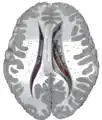

Coronal section through anterior cornua of lateral ventricles.